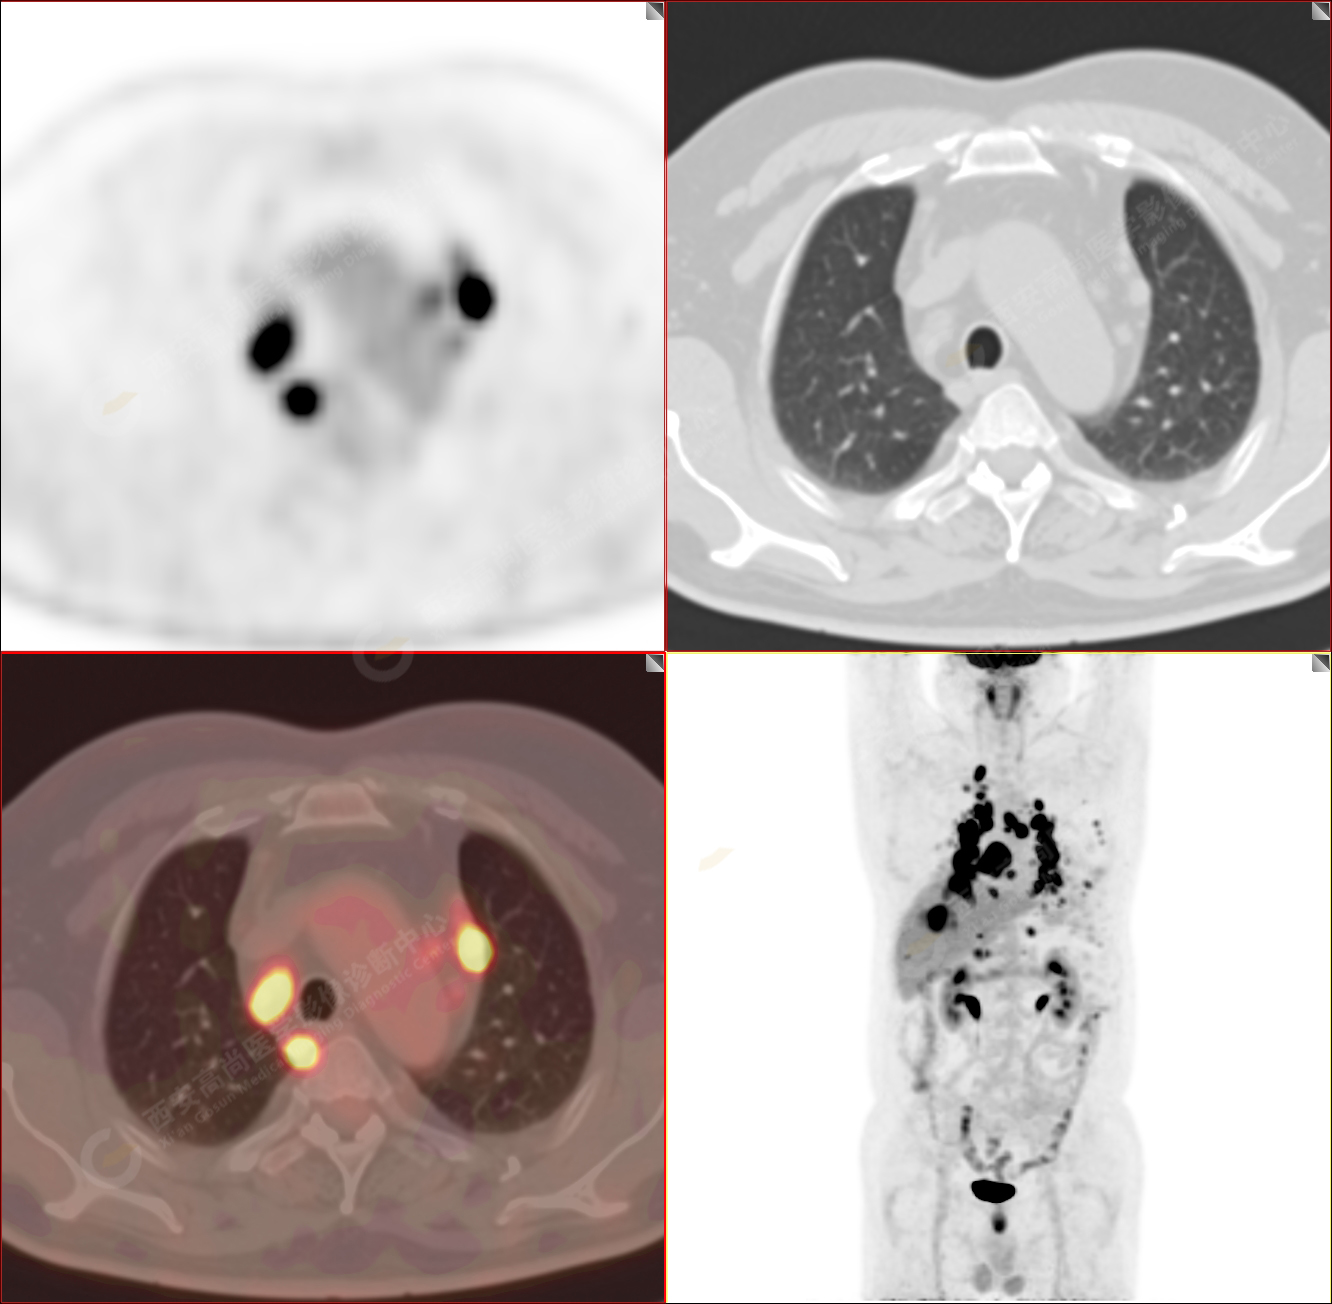

男性,53歲,頭暈半月入院,CT發(fā)現(xiàn)肺內(nèi)腫塊,雙肺多發(fā)大小不等實性及粟粒樣結(jié)節(jié),雙肺門及縱隔多發(fā)腫大淋巴結(jié)。病程中無發(fā)熱、胸悶氣及胸部不適。既往:左側(cè)肋骨外傷史。

PET/CT圖像